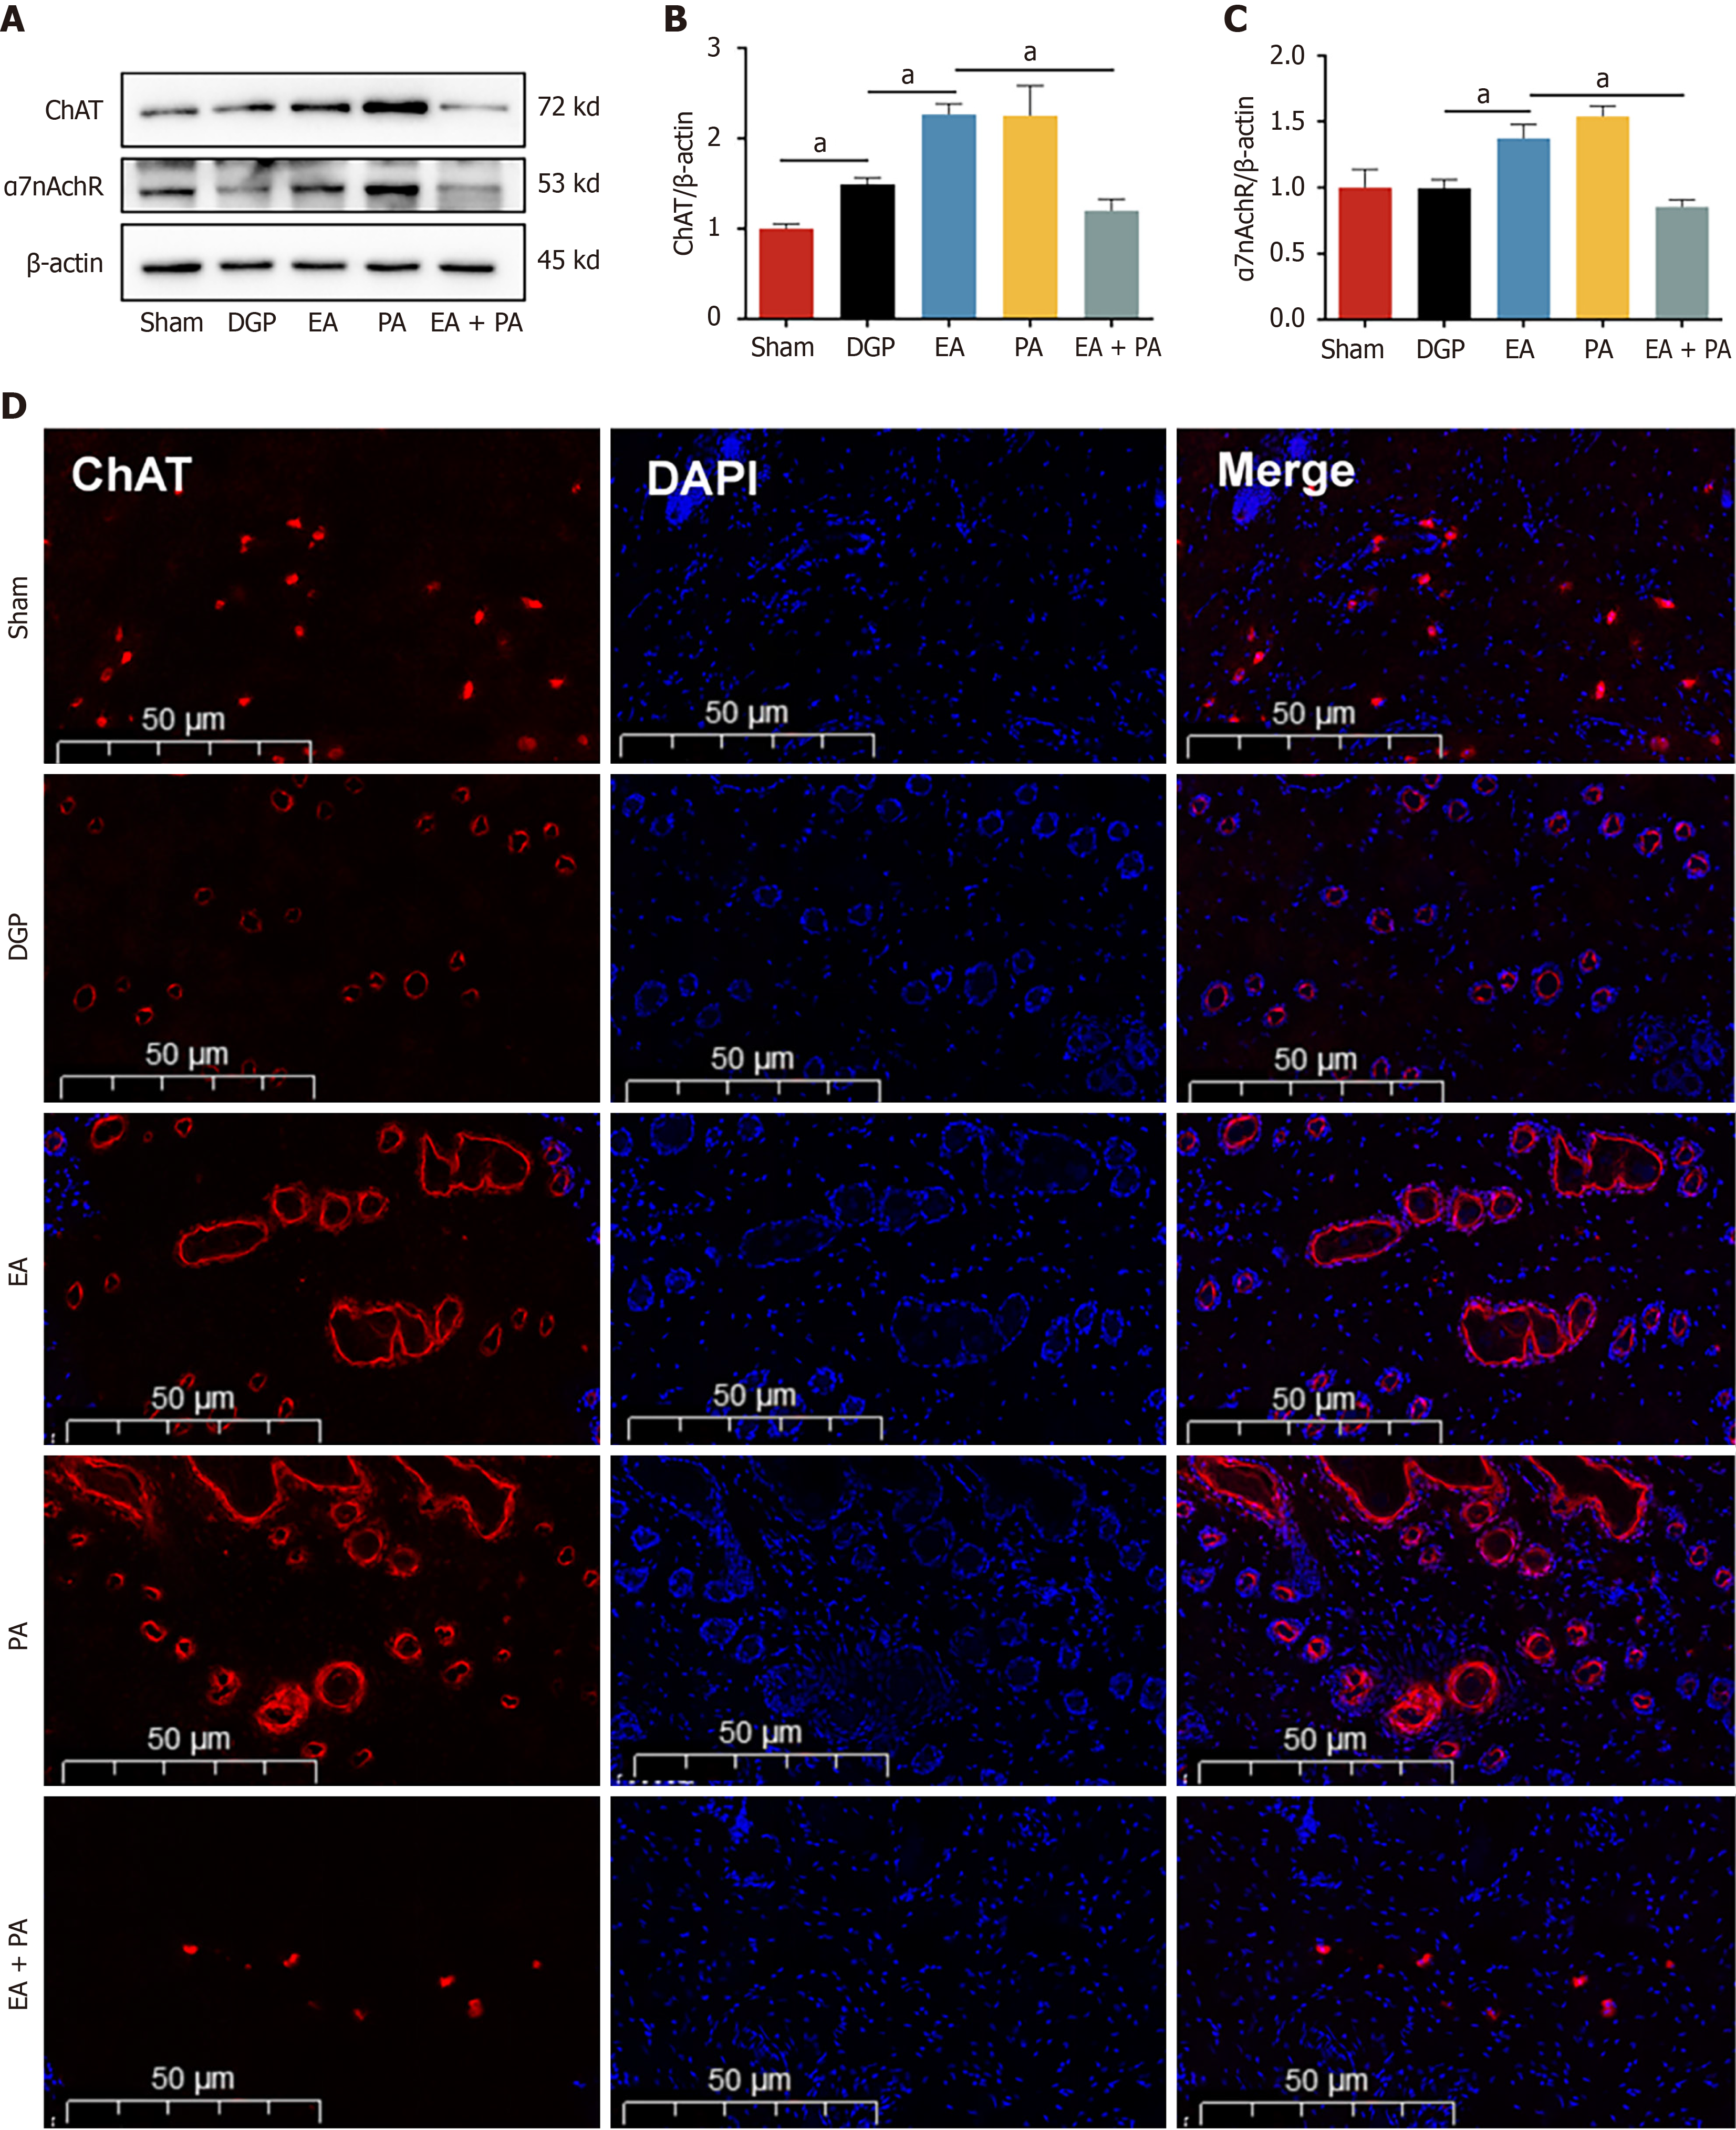

In order to elucidate the afferent neural pathways underlying EA-mediated gastric motility modulation in DGP rats, the ChAT inhibitor AP or the agonist PA was injected into the ST36 acupoint area and ChAT and α7nAChR protein expression was quantified across three key sites (Figures 4, 5 and 6): The ST36 acupoint skin, the spinal L4-L6 segments and the NTS (Figures 4A, 5A and 6A). Western blot analysis revealed significantly elevated ChAT levels in DGP rats compared to Sham controls across all sites (P < 0.05), with EA further amplifying ChAT expression (P < 0.05), mirroring trends observed in the PA group. However, the co-administration of AP with EA (EA + AP group) led to the abolition of this activation (P < 0.05; Figures 4B, 5B and 6B). In addition, EA induced an increase in α7nAChR expression in the ST36 skin, L4-L6 spinal region, and NTS (P < 0.05), an effect that was attenuated by AP co-treatment (P < 0.05; Figures 4C, 5C and 6C). Immunofluorescence analysis corroborated these observations. DGP rats exhibited reduced ChAT expression in ST36 skin, whereas EA and PA groups showed marked increases. AP administration nullified EA’s effects (Figure 4D). In the spinal L4-L6 segments, c-FOS immunostaining revealed robust neuronal activation in the EA and PA groups (P < 0.05), which was suppressed in the EA + AP rats (P < 0.05; Figure 5D). c-FOS +/ChAT + co-localization further confirmed that this activation was ChAT-dependent (Figure 5E). In the NTS, c-FOS expression was significantly elevated in the EA and PA groups (P < 0.05), with EA + AP rats showing reduced activation (P < 0.05; Figure 6D). c-FOS +/ChAT + co-expression mirrored these trends, demonstrating EA’s dual modulation of neuronal activity and cholinergic signalling (Figure 6E). The data taken together indicate that EA activates vagal ChAT/α7nAChR targets at ST36, transmitting signals via spinal L4-L6 afferents to NTS neurons, thereby restoring vagal tone in DGP.